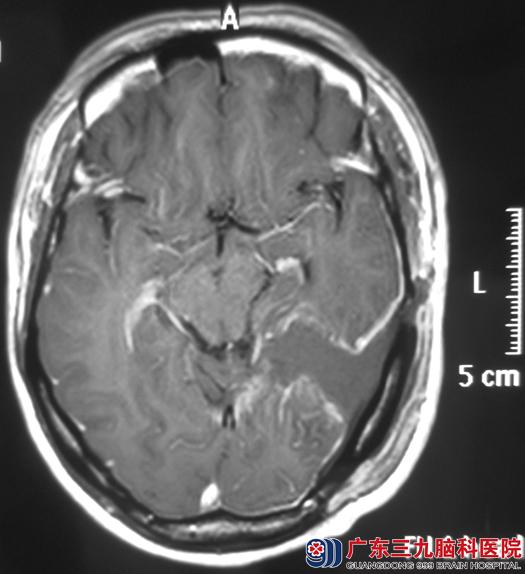

完善检查后,由鲁明主任主刀,在全麻下行左侧颞枕部小脑幕上脑膜瘤切除术,术中显微镜下见淡红色肿瘤组织,质软、血供丰富、边界清楚,肿瘤基底位于小脑幕上,分块完整切除。术后病理结果为:过渡型脑膜瘤(WHO I级)伴钙化。

手术后